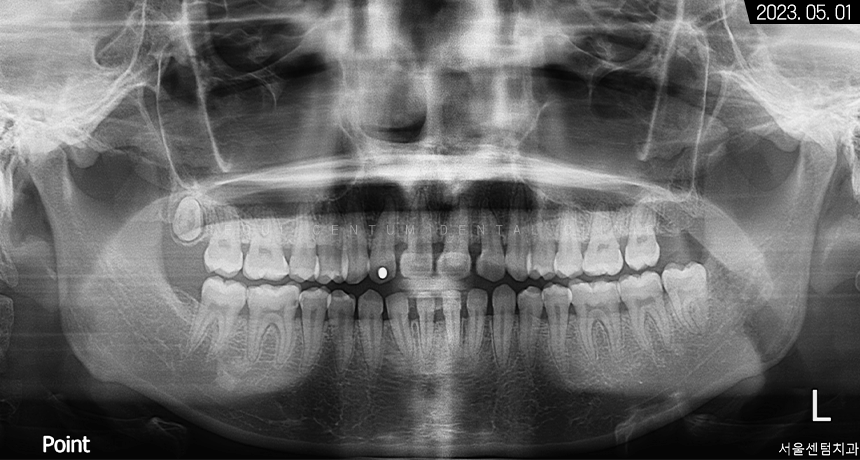

이번에 찾아오신 분의 파노라마 사진을 보면

치아가 굉장히 빽빽하게 들어차있는 것과

전형적으로 구강 내 협소한 자리로 인해

치아 전돌이 형성된 케이스라는 것을

알 수 있습니다.

하악 좌측 사랑니도 보이고

상악 우측 사랑니까지 맹출 된 것을 볼 수 있었고요.

앞니끼리 공간이 부족해 겹친 것이 확인되었고

부분적으로 치간이개를 갖고 계셔서

그 공간을 폐쇄하면서 치간 삭제를 동시에 한다면

돌출 정도가 어느 정도 해소될 것으로 예상됐습니다.